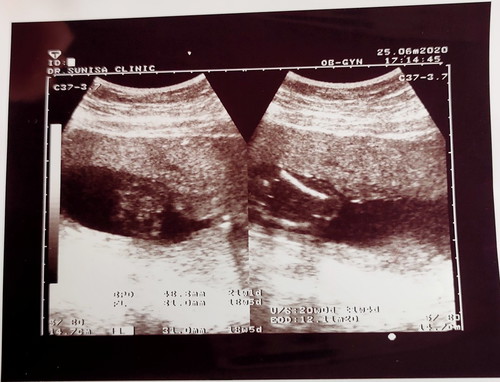

แม่ดูใบซาวน์ไม่ออกค่ะ ส่วนไหนเป็นส่วนไหน

แม่ไปซาวน์คลินิกมา คุณหมอบอกแค่ว่า อาจจะเป็นผู้ชาย ส่วนรายละเอียดในใบซาวน์ คุณหมอไม่บอกเลย รบกวนแม่ๆช่วยดูให้หน่อย ขอบคุณค่ะ

ใบซาวด์จะไม่มีระบุเพศค่ะ ระบุแค่ขนาดต่างๆที่หมอ ในภาพจะมีรูปกระดูกต้นมา กับหัวค่ะ อายุครรภ์20สัปดาห์